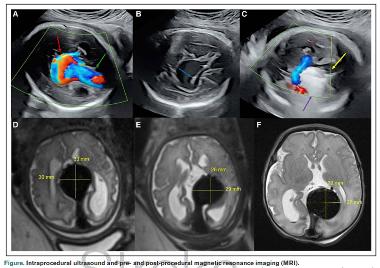

Врачи выявили у плода врожденный порок развития - артериовенозную мальформацию вены Галена на 30 неделе гестации с помощью ультразвукового исследования. Магнитно-резонансная томография на 32 неделе подтвердила диагноз и расширенное соединение вены Галена и задней части верхнего сагиттального синуса.

Было принято решении о проведении оперативного лечения. На 34 неделе гестации под спинальной эпидуральной анестезией врачи вручную перевернули плод, под контролем ультразвука ввели иглуввели в череп плода в зону пораженных сосудов, по катетеру провели неполную эмболизацию шунта.

МРТ после эмболизации показала, что диаметр соединения вены Галена и верхнего сагиттального синуса сократился с 12,9 миллиметра до 8 миллиметров. Кровоток в этой области значительно снизился. Из-за преждевременного разрыва плодных оболочек младенец родился естественным путем через два дня после операции. Вес при рождении составил 1,9 килограмма.